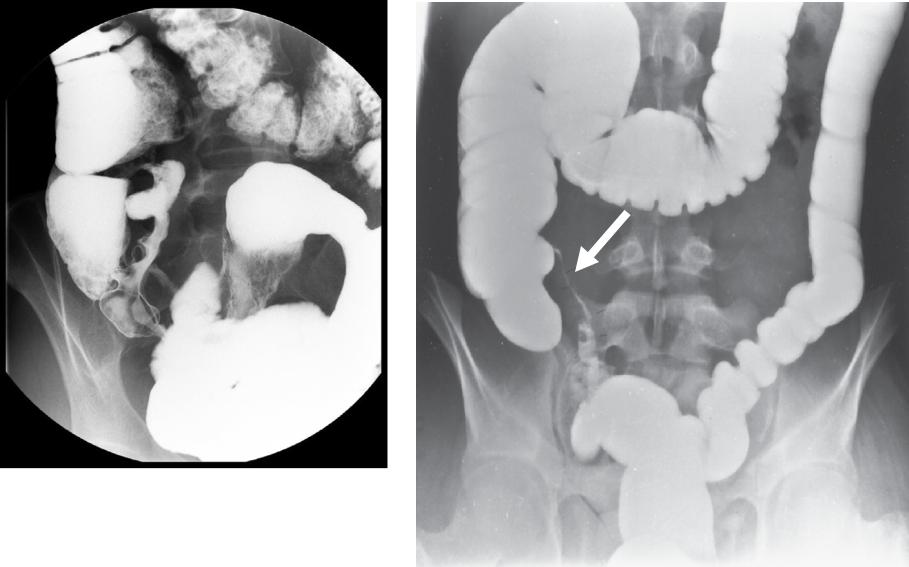

Болезнь Крона: рентгенологические признаки